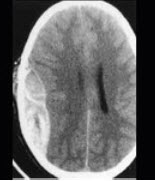

男性,50岁,摔跤后出现头痛2天入院,行头颅CT出现如图所示病变,应诊断为( )

A:硬膜外出血

B:蛛网膜下隙出血

C:脑梗死

D:硬膜下出血

E:脑出血